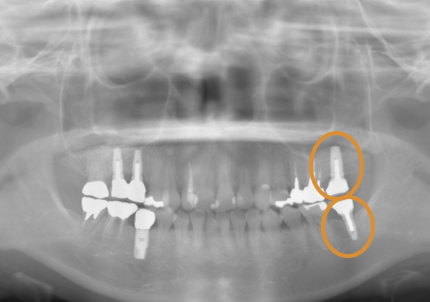

11.経過レントゲン

↑2006年4月24日

↑2008年12月